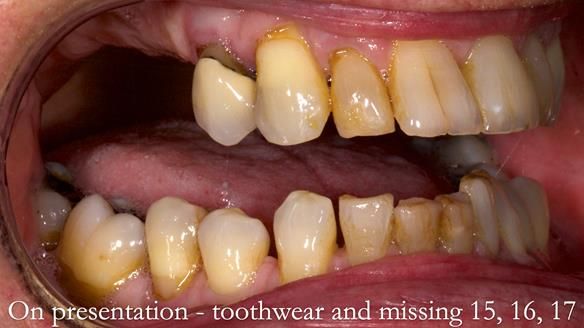

Welcome to Newsletter 64. I'll walk you through the process of providing a Mk 2 metal-based partial denture (RPD), for Ian a retired Veterinary Surgeon aged 78. The RPD was made at an increased vertical dimension and acted as an occlusal stabilisation splint - reducing the wear and bite force on the remaining natural teeth.

Ian was referred to me by his general dentist.